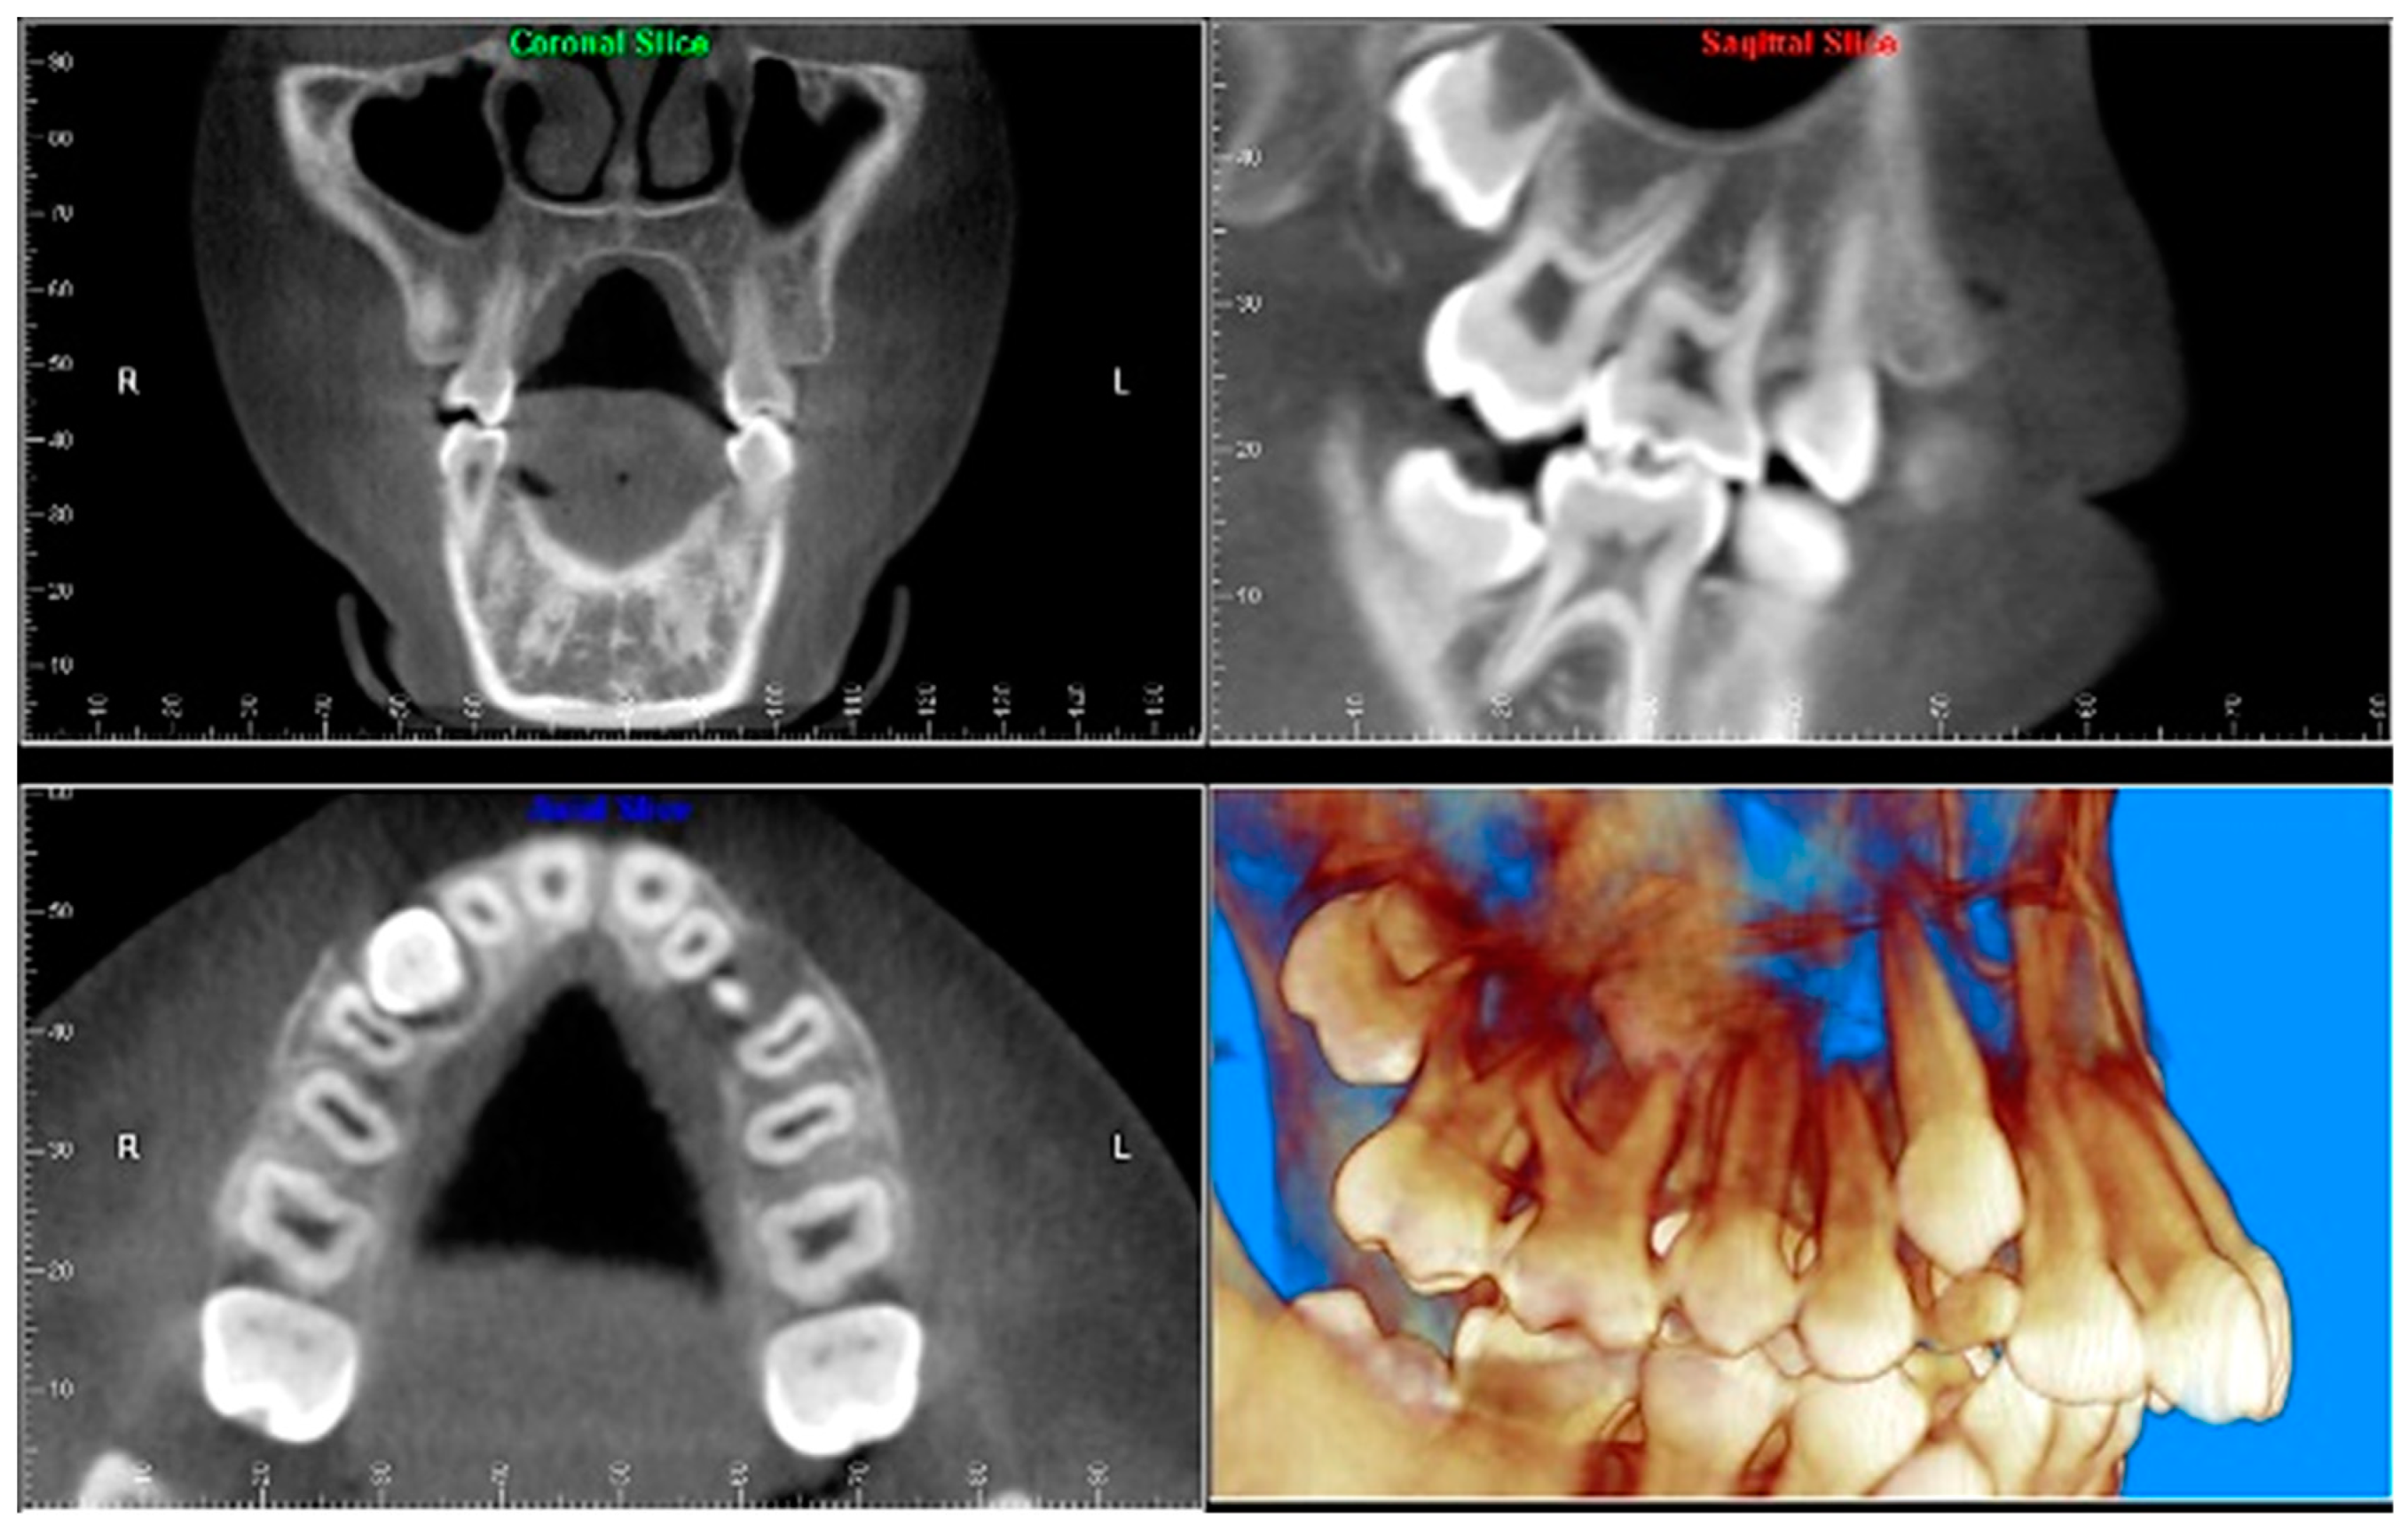

- Evaluation of impacted teeth, a common indication of CBCT in orthodontics. The advantages of CBCT include assessment of the tooth location and position, the stage of development, and status of adjacent teeth. CBCT is justified in these cases, because CBCT has the capability of evaluating the impacted teeth and adjacent structures more accurately than 2D conventional imaging. The benefit–risk ratio is favorable, especially if the CBCT volume is collimated to the impacted tooth. Figure 1, Figure 2, Figure 3 and Figure 4 show an example of impacted maxillary canines, and their proximity to the maxillary lateral incisors. Figure 1 shows an intraoral photograph. The benefit of CBCT acquisition in this case includes the ability to visualize the canines and the lateral incisors in three dimensions, which can be visualized in Figure 2 and Figure 3. In this case, the maxillary right lateral incisor exhibited external root resorption, a finding that would be difficult to see on a conventional 2D panoramic radiograph. Figure 4 shows a Maximum Intensity Projection of a panoramic view derived from the CBCT volume. This unique view is free of magnification, distortion, ghost images, and overlaps frequently seen in conventional 2D panoramic radiography.